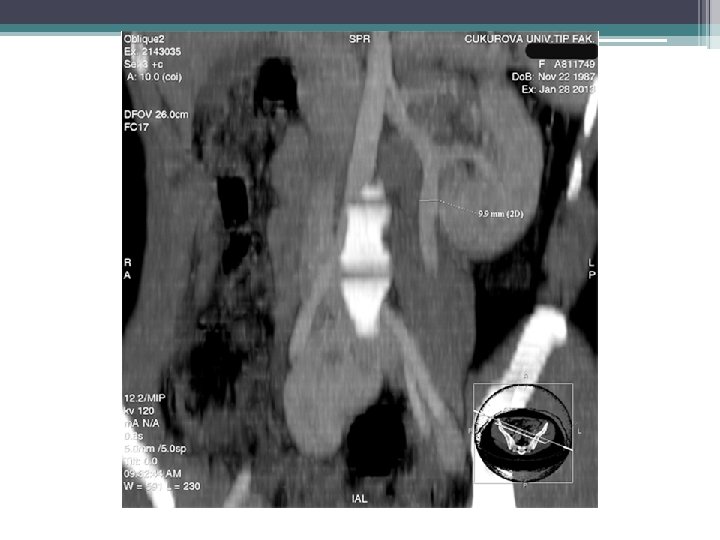

ACİL BAŞVURU (1. ay) • ŞİKAYET: Sol bacakta şişlik, ciddi ağrı, hareket kısıtlaması • RDUS: Sol eksternal iliak, ana femoral ven proksimalinde nonkanalize akut tromboz

VENOGRAFİ

ASPİRASYON TROMBEKTOMİ VE TROMBOLİZİS SONRASI